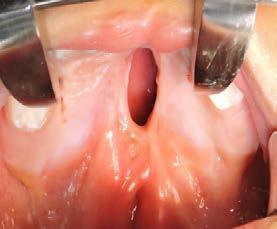

Por lo que se propone procedimiento quirúrgico con la evidente comunicación oroantral al realizar las extracciones de los órganos dentales involucrados. Previa asepsia y antisepsia, colocación de campos estériles, extracción de segundo y tercer molar superior derecho e incisión envolvente con descarga mesial (Figura 3), rotación y afronte mediante puntos simples de la bola adiposa de Bichat para el cierre de la comunicación oroantral (Figura 4), farmacoterapia con base en amoxicilina con ácido clavulánico. Una semana después refiere no presentar rinorrea y mejoría al 100% de la obstrucción. Posterior a 6 meses de evolución clínica (Figura 5) y radiográficamente (Figura 6), no se observa comunicación oroantral o paso de líquidos de la cavidad oral a la cavidad nasal.

4. Cierre de comunicación con la bola adiposa de Bichat.

Figura 3. Colgajo envolvente con liberatriz mesial y alveolo postextracción.

Figura